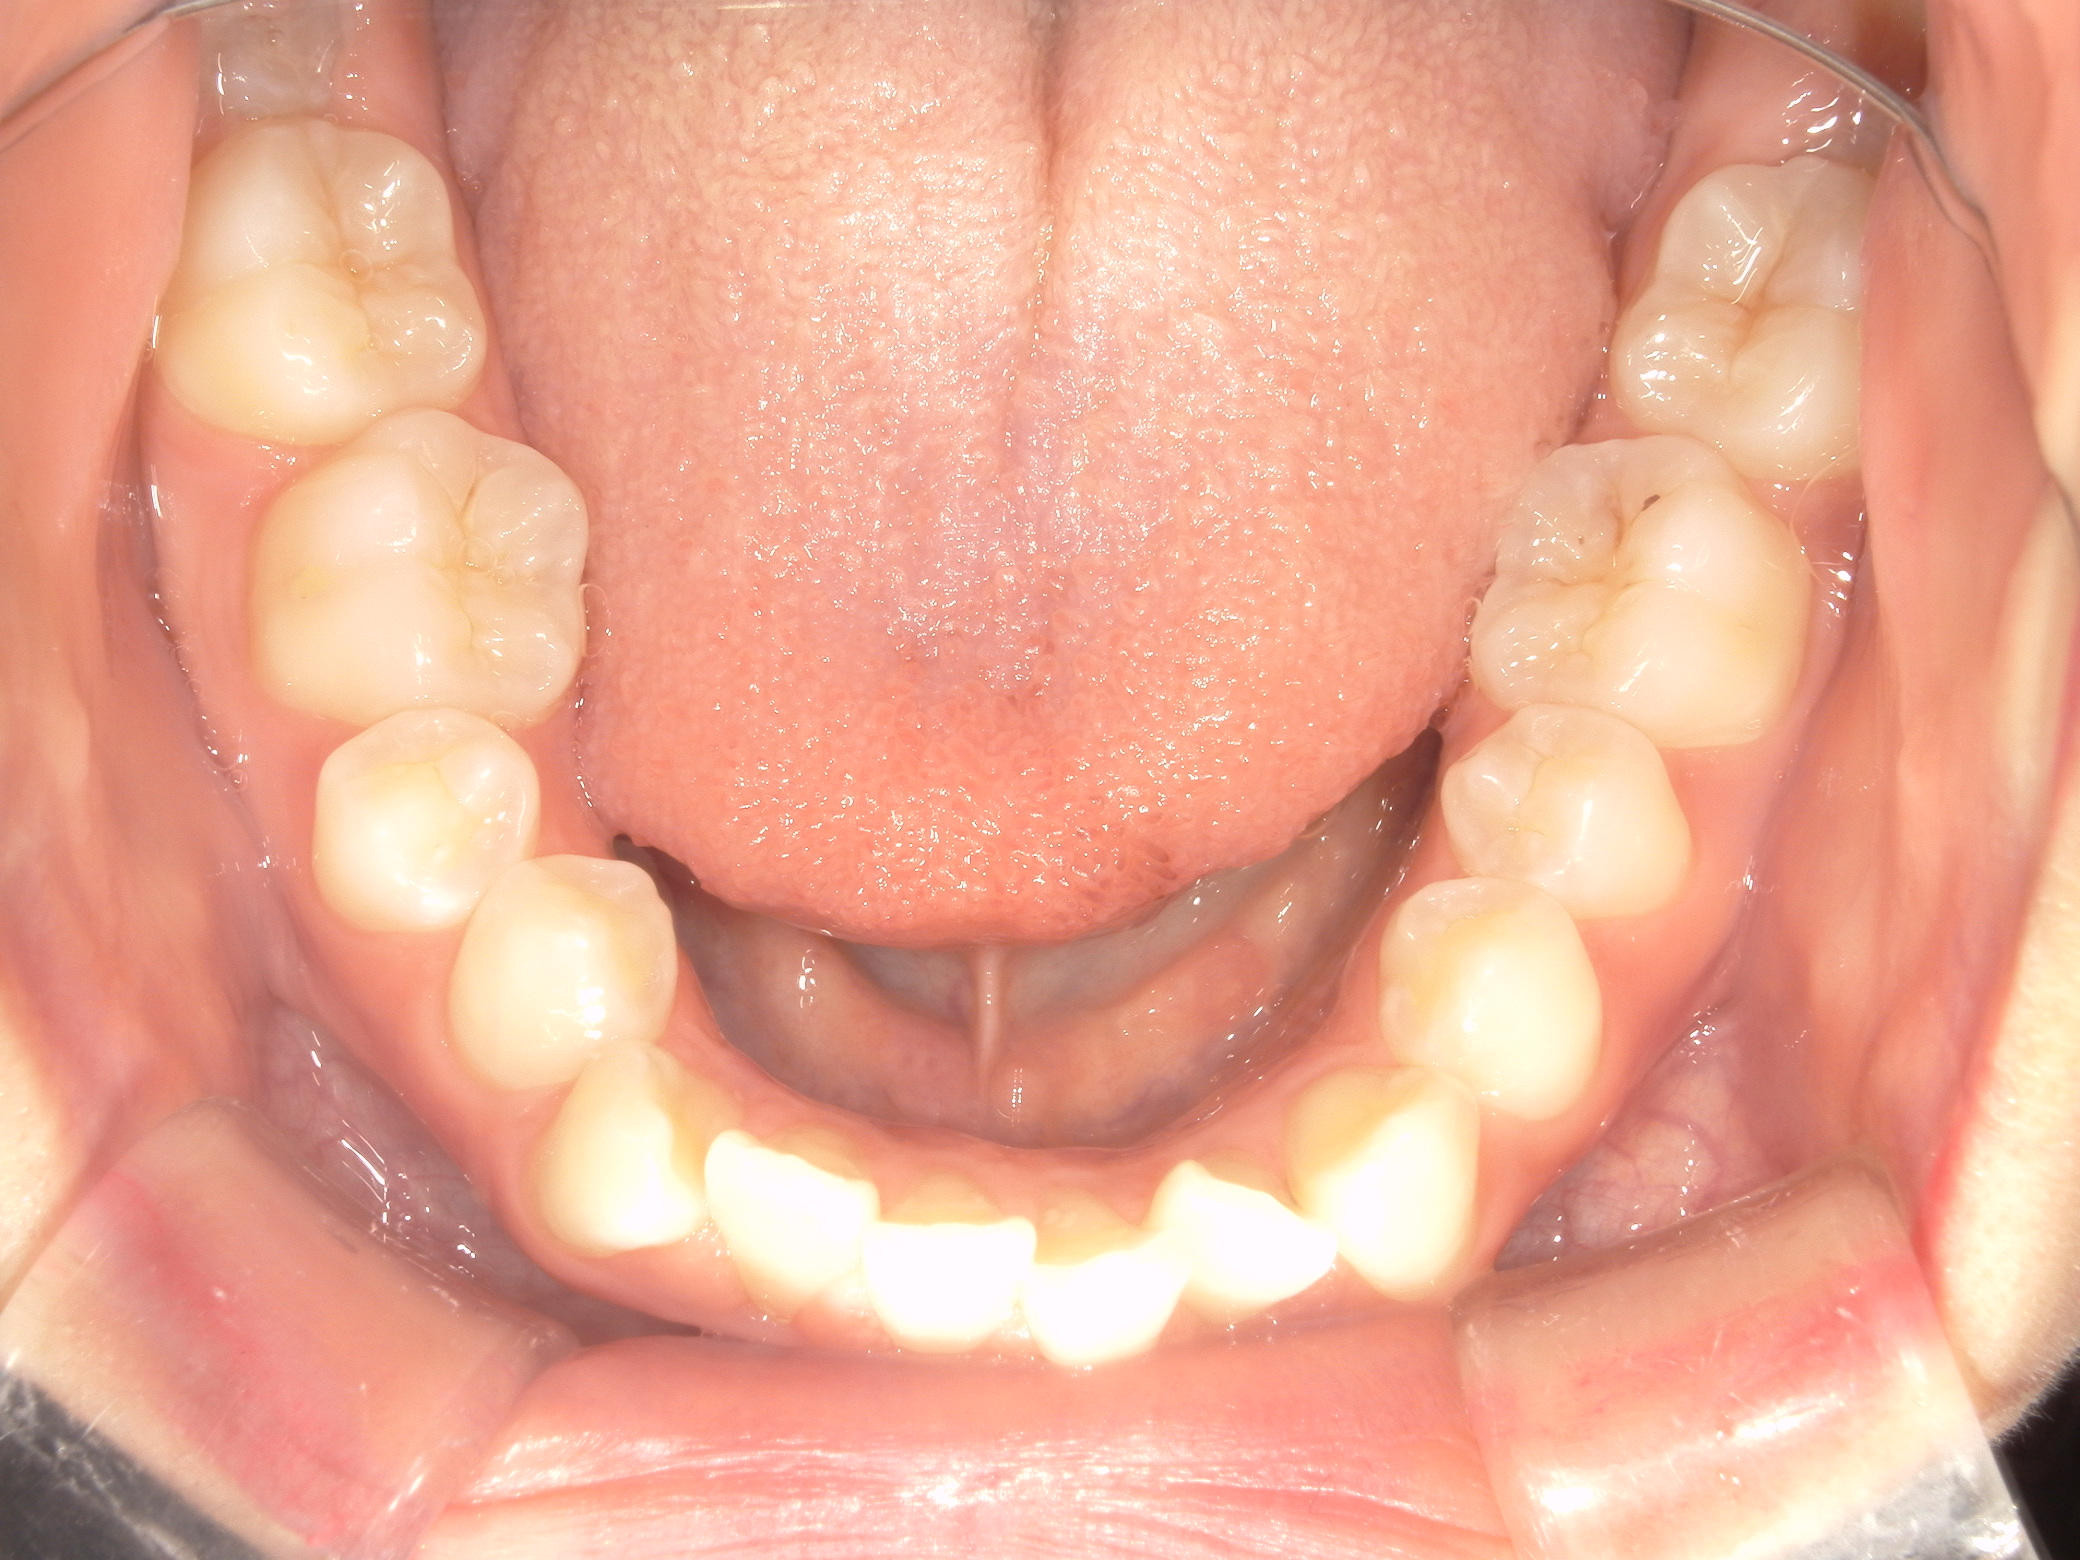

プチワイヤー矯正 症例(54)

主訴: 歯並びが気になる。

カテゴリー : ガタガタ(叢生)